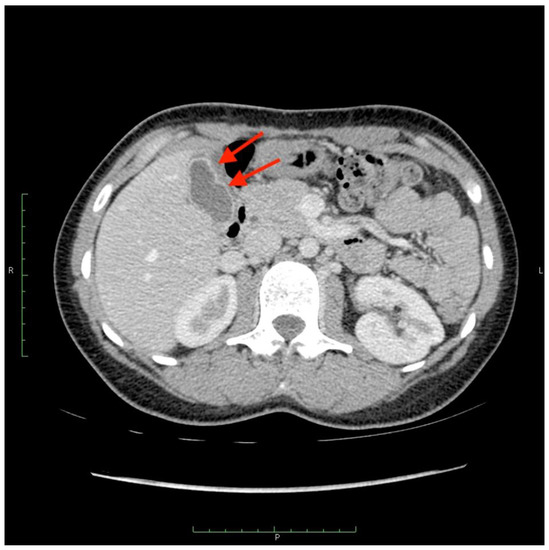

Figure 7.

A computed tomography scan depicting asymptomatic cholecystitis (arrows) after the 90Y leak. The patient did not require surgery and was treated conservatively.